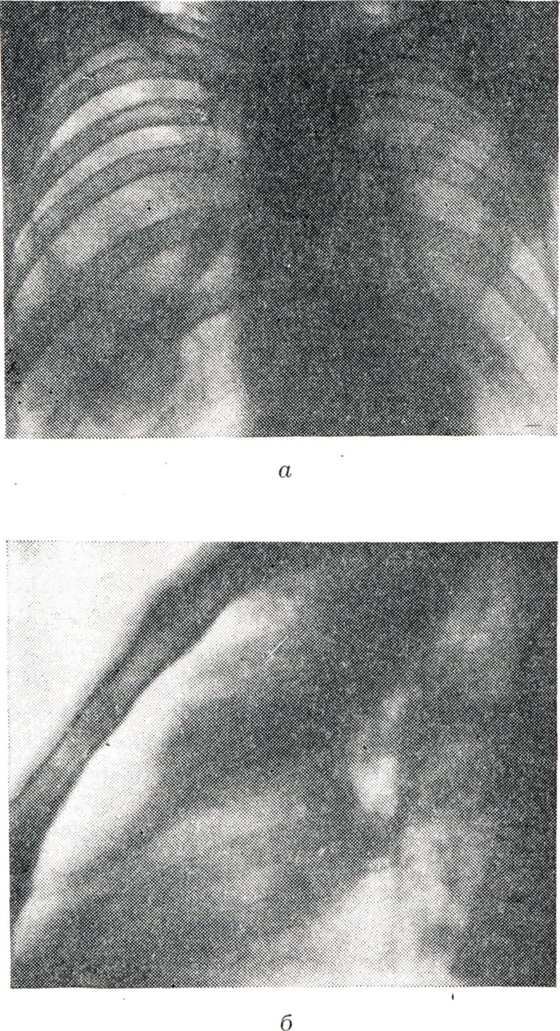

При тотальном ателектазе (рис. 3, 1 и 2) спавшееся легкое обычно уменьшено, интенсивно и равномерно затемнено. В большинстве случаев тени ребер сближены (соответственно западению грудной стенки), иногда наблюдается сколиоз грудного отдела позвоночника, выпуклостью обращенный в сторону поражения. Купол диафрагмы и тени поддиафрагмальных органов на стороне ателектаза приподняты; слева необычно высоко и медиально проецируется газовый желудочный пузырь. Срединная тень, в частности трахея, значительно перетянута в сторону ателектаза, бифуркация трахеи проецируется сбоку от тени позвоночника. Непораженное второе легкое вздуто, и его тень частично перемещена в противоположную половину грудной клетки. Такое перемещение испытывают главным образом передне-верхние позадигрудинные отделы противоположного легкого, давая в рентгенологическом отображении картину так называемой медиастинальной грыжи, то есть ограниченное дугообразной линией просветление на фоне верхне-медиальных отделов затемненного легочного поля на стороне ателектаза. Такие «грыжи» могут достигать больших размеров, в особенности при ателектазе левого легкого. Рентгенологическая картина при долевых ателектазах типична (рис. 3, 3—12). Как известно, доли легких как бы фиксированы в двух местах: у корня и из-за отрицательного внутриплеврального давления у грудной стенки. В силу эти особенностей спадение и перемещение долей легких при ателектазе происходит в случае отсутствия плевральных сращений закономерно в определенном направлении. Верхняя доля правого легкого смещается при ателектазе кверху, кнутри и кпереди в направлении передне-медиальных отделов грудной клетки. Нижняя граница тени спавшейся доли (линия малой междолевой щели) перемещается кверху, задняя (линия главной междолевой щели) — кпереди. На боковой рентгенограмме определяется треугольная тень с несколько втянутыми гладкими контурами, вершина которой примыкает к тени корня, а основание — к грудной стенке. На фоне этой тени хорошо видна линия косой междолевой щели, переместившейся кпереди. При нарастающем спадении доли последняя приближается к грудной стенке и исчезает. Спадение верхней доли может быть столь значительным, что на прямой рентгенограмме ее тень представляется узкой боковой полоской у средостения, а в боковой проекции — симулирует уплотнение легочного сегмента. Ателектаз верхней доли сопровождается расширением нижней и средней долей, наибольшему вздутию подвергаются задне-верхние отделы нижней и верхне-передние отделы средней доли. Тень корня легкого перемещается, как правило, кверху. При ателектазе правой верхней доли, как и при ателектазах других долей, наблюдаются и атипичные картины, нередко симулирующие на передней рентгенограмме картину медиастинальной «грыжи», что обусловлено главным образом плевральными сращениями, фиксирующими легкое. Рентгенологическая картина ателектаза верхней доли левого легкого отличается большим объемом, более отвесным расположением левой косой междолевой щели и не всегда четкой нижней границей тени: в части случаев она дугообразно втянута. Средняя доля при ателектазе смещается кнутри и кпереди. Верхняя граница ее перемещается книзу, нижняя, соответствующая косой междолевой щели, — кверху и несколько кпереди. На прямой рентгенограмме спавшаяся доля проецируется в нижне-медиальных отделах легочного поля; тень ее обычно треугольной формы, имеет вогнутые верхний и нижний контуры или же втянутый или прямолинейный нижний и слегка выпуклый верхний контур. В боковой проекции тень имеет также форму треугольника с ровными и чаще втянутыми контурами либо форму полосы, овала, полуовала с выпуклой верхней и прямолинейной или втянутой нижней границей. При резком уменьшении средней доли она может быть представлена на прямой рентгенограмме нехарактерным малоинтенсивным затемнением, и лишь исследование в боковом или лордотическом положении позволяет выявить тень, характерную для ателектаза средней доли. Тень корня перемещается обычно книзу. Нижние доли обоих легких смещаются при ателектазе книзу, кнутри и кзади. На прямой рентгенограмме уменьшенная доля имеет форму треугольной тени, вершиной обращенной к корню и основанием к диафрагме. Наружная граница тени несколько втянута, иногда — выпуклая или прямолинейная. При большом уменьшении доли определяется небольших размеров треугольная тень у контура позвоночника, которая может быть перекрыта слева тенью сердца. В боковой проекции тень спавшейся доли частично наслаивается на тень позвоночника; видна линия переместившейся кзади косой междолевой щели. Спадение нижней доли сопровождается вздутием верхней, а справа — и средней доли; тень корня смещается книзу и кнутри. Сегментарный ателектаз имеет менее характерную рентгенологическую картину, тень его нередко симулирует картину сегментарного уплотнения воспалительной природы. Вторичные симптомы обычно не выражены. Как правило, сегментарный ателектаз не вызывает западения грудной стенки и изменений противоположного легкого. Обычно спадение сегмента сопровождается перемещением лишь граничащих с ним отрезков междолевых щелей, вздутием соседних отделов легкого. Симптом Гольцкнехта — Якобсона при сегментарном ателектазе выражен недостаточно отчетливо. Иногда диагноз может быть установлен лишь с помощью томо¬графии или бронхографии. Рентгенологическая картина ателектаза отдельных сегментов легкого представлена на схеме (рис. 4). Дольковые и ацинозные ателектазы обычно бывают множественными. Рентгенологически они не отличимы от теней очаговой пневмонии, с которой нередко сочетаются. При большом числе дольковых ателектазов, занимающих большую часть легкого, наблюдаются вторичные симптомы ателектаза, в частности положительный симптом Гольцкнехта—Якобсона. Дисковидные, или пластинчатые, ателектазы, расположены обычно низко над диафрагмой; рентгенологически имеют форму поперечно расположенных полосовидных теней (рис. 5) шириной существовании дисковидного ателектаза соответствующий участок легкого может подвергнуться рубцовому превращению.